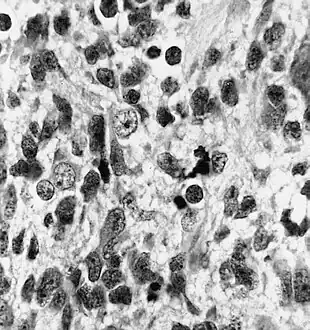

Neuronal differentiation, ranging from neuroblasts to ganglion cells, is seen in some medulloepitheliomas.

Immunohistochemically, neural tube-like structures are vimentin positive in the majority of medulloepitheliomas.[11] Poorly differentiated medulloepitheliomas are vimentin negative.